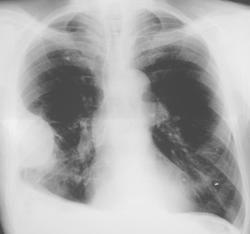

Данная фокусная тень с грудной стенкой образует «тупые углы». Справа над диафрагмой определяется снижение прозрачности легочной ткани значительной интенсивности, однородной структуры с косой верхней границей. Иллюстрация 1 – флюорограмма пациента, проведенная за 6 месяцев до этого обращения с профилактической целью. Скиалогическая картина фиксирует возрастные изменения.